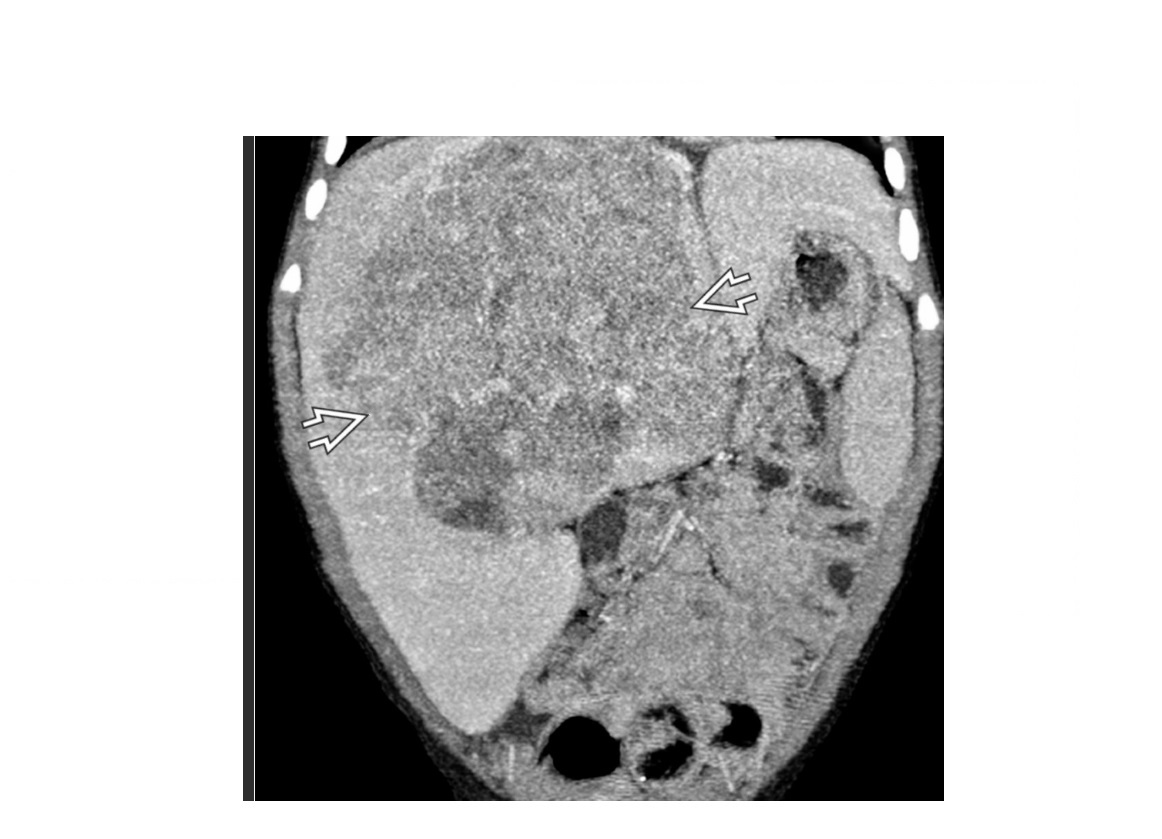

Painless abdominal mass, 6 year old child. US - large well defined solid heterogenous liver mass with raised AFP?

A

Hepatoblastoma

Coarse calcification

Precocious puberty is highly specific but rare.

Most common malignant hepatic tumour of childhood.

Young adolescents = HCC

Associated with* Beckwith Wiedemann syndrome. *

Can invade the vessels